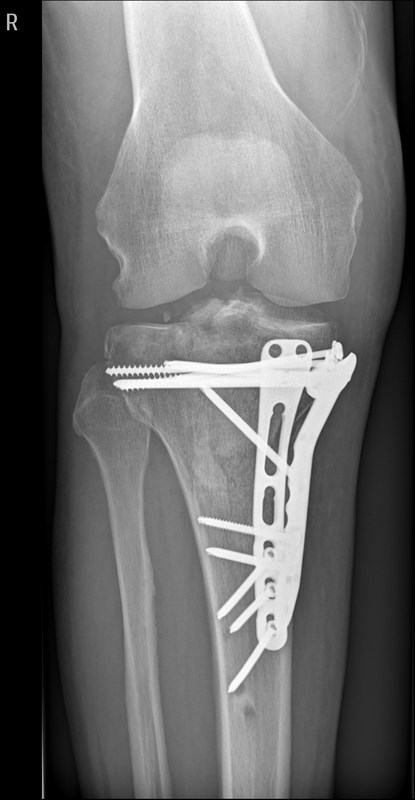

Lange Rede, kurzer Sinn, Schienbein rechts innen durch den Zylinder zerschmettert!

Erstes O.P. Externer fixateur,

Zweiter O.P.-Bissjen titanium.